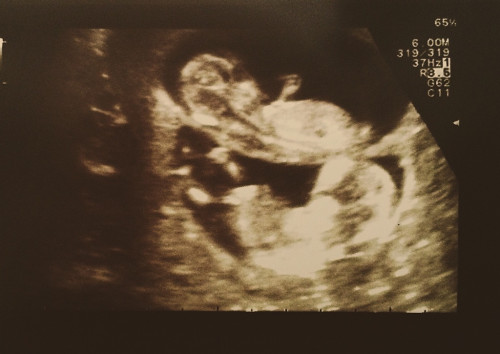

А вот и наши малыши!

5).

мое тоже прикольное. Мои девочки валетиком лежат и палец вам показывает одна) особено супер фотогурманам)) 😂😂😂

Сейчас уже их положение совершенно другое. Прикольно оно мне, застали один единственный разок))